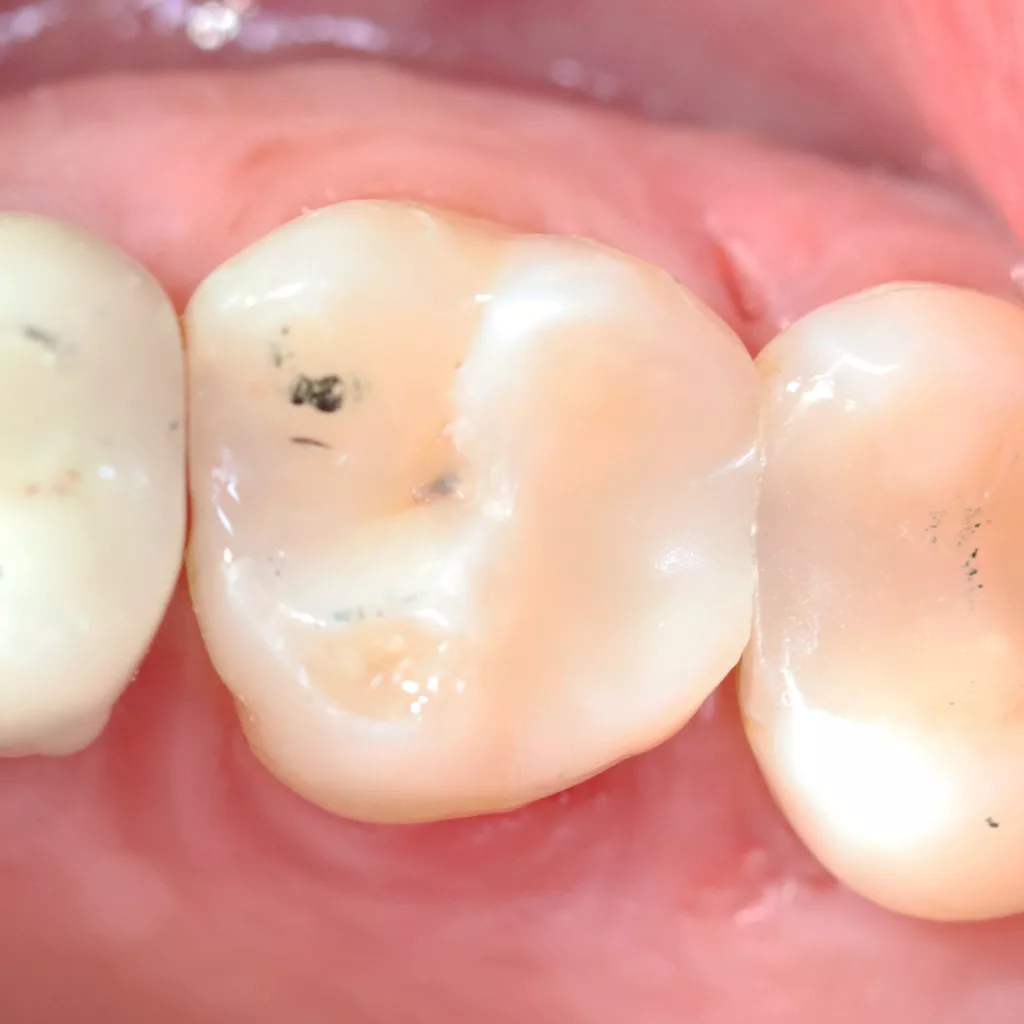

Wird eine profunde kariöse Läsion behandelt, empfiehlt sich folgendes Vorgehen [5]: Zunächst sollte in einem ersten Schritt ein Kofferdam appliziert werden, um eine möglichst keimfreie Arbeitsweise zu gewährleisten. Nach Präparation einer Zugangskavität, wenn dies notwendig ist, erfolgt die Kariesexkavation mittels Rosenbohrern oder Handexkavatoren. Wird in pulpanahen Arealen eine Eröffnung der Pulpa erwartet, sollte das Instrument gewechselt und ein sauberer Rosenbohrer genutzt werden. Tritt nach vollständiger Kariesexkavation keine Eröffnung der Pulpa ein, ist aber von einer dünnen Restdentindicke von etwa 300 µm auszugehen, oftmals erkenntlich durch eine zartrosa hindurchschimmernde Pulpa, sollte nach Kavitätentoilette mittels Natriumhypochlorit (NaOCl) 3% eine indirekte Überkappung mit einem hydraulischen Kalziumsilikatzement erfolgen [5]. NaOCl dient dazu, Bakterien und Toxine zu neutralisieren und das Dentin zu desinfizieren. Die Unterfüllung aus Kalziumsilikatzement soll auch desinfizierend wirken, das Pulpagewebe zur Heilung anregen und vor möglicherweise durch das Dentin penetrierenden Monomeren aus dem Dentinadhäsivsystem schützen [5], da diese die regelrechte Funktion der Odontoblasten beeinträchtigen können [9,40]. Im Anschluss muss eine direkte, dentinadhäsive Restauration zur Versorgung der Kavität platziert werden [5]. Die Abbildungen 1 bis 14 illustrieren das Vorgehen bei der Behandlung einer profunden kariösen Läsion mit indirekter Überkappung der Pulpa.